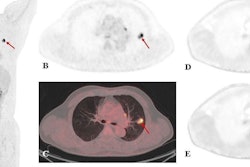

To quantify these developments, the group analyzed administered doses in 243 children and adolescents who underwent 466 clinical F-18 FDG-PET/CT or PET/MRI scans of the body at their hospital between January 2000 and May 2021. They measured exposure in megabecquerels (MBq), with standard recommended doses ranging between 2 and 5 MBq per kilogram.

The median injected F-18 FDG activity dropped from 296 MBq in 2000-2005 to 100 MBq in 2016-2021, equaling approximately one-third of the initial amount, the group found. Over time, the reduction ranged from −57% up to −84%, depending on the age group, with the smallest reduction observed in the youngest patients.

In addition, signal-to-noise ratio (SNR), an objective surrogate for image quality, remained stable during all years, they added.